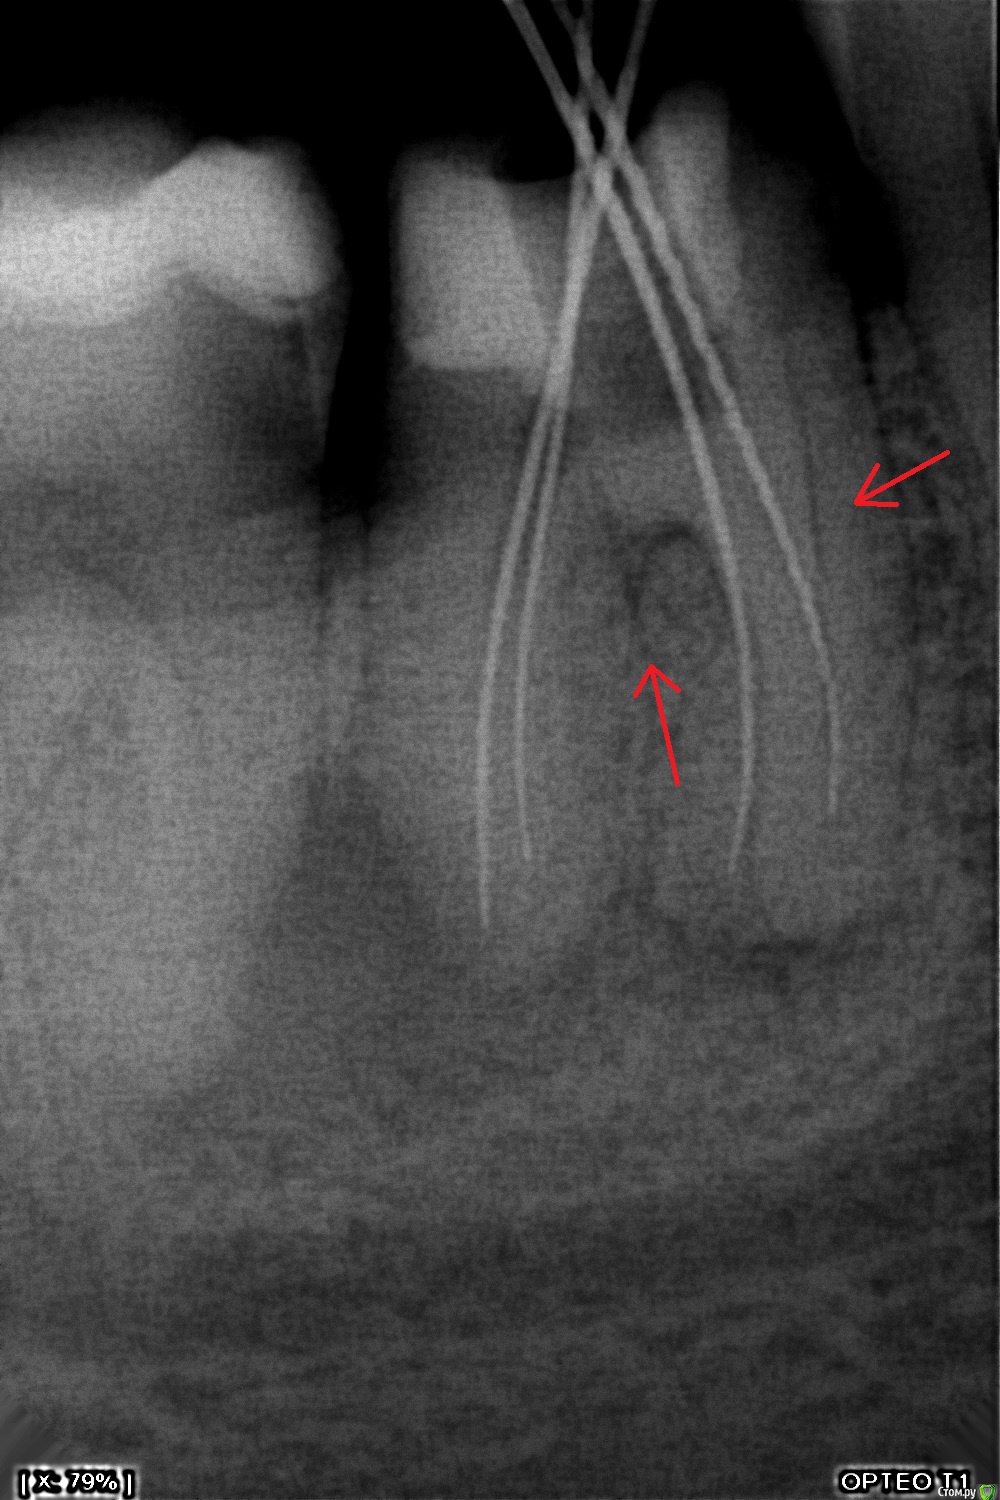

St. Опубликовано 29 сентября, 2015 Автор Поделиться Опубликовано 29 сентября, 2015 (изменено) 36 зуб, плановая ревизия перед постановкой коронки. Асимптоматичен. Довольно плотная РФП. Дистальный и мед/щечный "допилила" ещё до 0 по апексу. В мед/яз упираюсь в ступень. Оставила кальций.Попробую подолбаться в следующий визит ещё. Что бы вы делали, если не получилось обойти? Изменено 29 сентября, 2015 пользователем St. Ссылка на комментарий